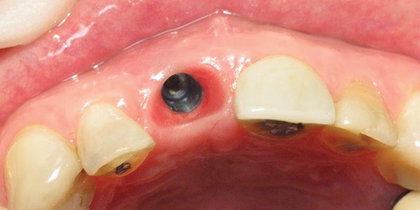

• A central incisor is extracted and immediately replaced with a Glidewell HT Implant and provisional crown, facilitating an esthetic final outcome. thumbnail image

Immediate Provisionalization

A central incisor is extracted and immediately replaced with a Glidewell HT Implant and provisional crown, facilitating an esthetic final outcome.